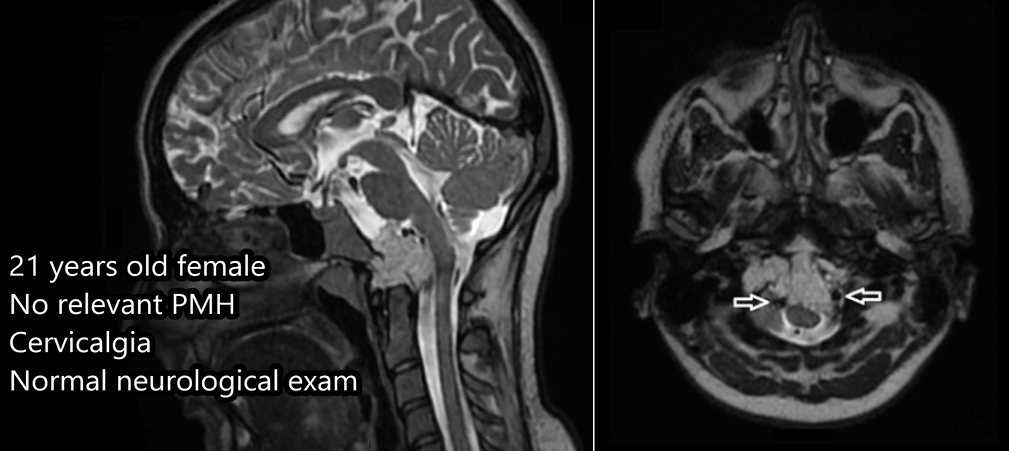

病例三:一位21岁女性患者,因颈部疼痛检查发现枕骨大孔和颅颈交界区存在脊索瘤,病变扩展至硬膜内。该脊索瘤患者还伴有明显的骨质破坏和硬膜内延伸表现。

病例三:21岁女性脊索瘤

年轻女性因颈部疼痛就诊,MRI发现颅颈交界区脊索瘤,伴骨质破坏和硬膜内延伸,累及双侧椎动脉。